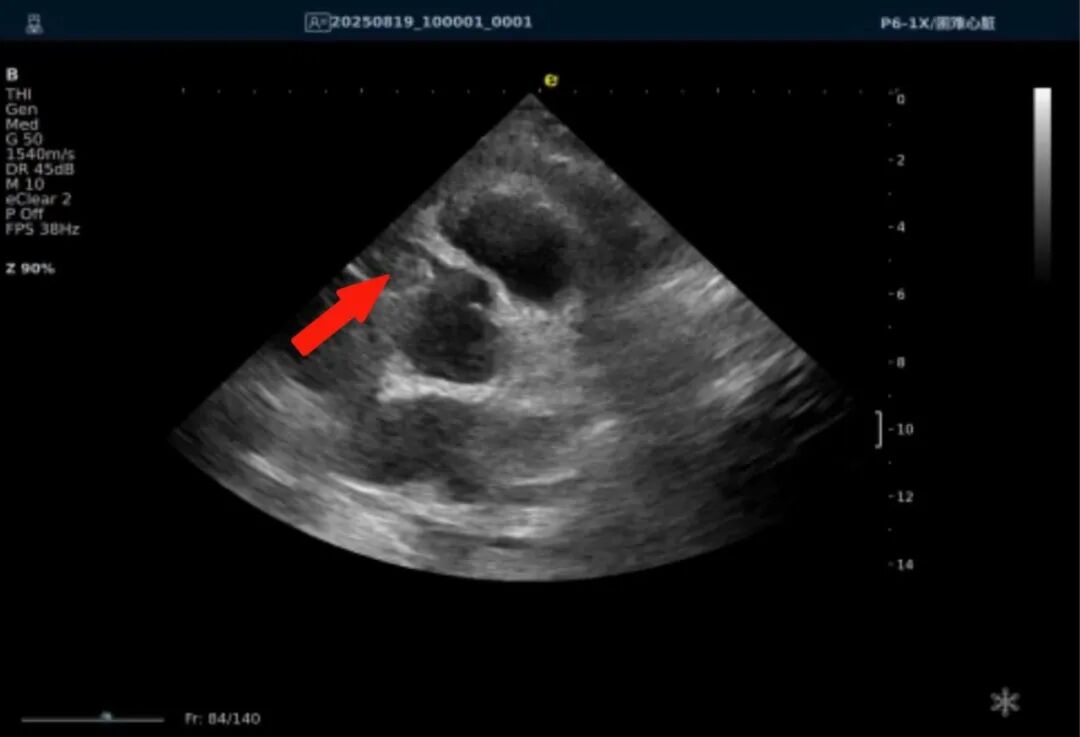

以下为逸超医疗(ESI)设备采集的冠脉图像,清晰展示了其在二维成像、彩色多普勒及频谱多普勒方面的表现:

左右滑动查看更多

心脏冠脉超声